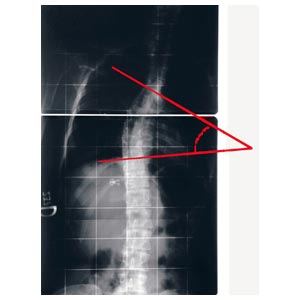

Strumento per la misurazione dell'angolo di Cobb e del gibbo. L'inclinometro è costituito da 1 elemento quasi-rettangolare di plexiglas recante una scala goniometrica, al cui centro è posizionata una piccola asta libera di ruotare e recante una bolla; l'estremità libera dell'astareca l'indice di lettura per la scala goniometrica. Il lato più lungo del rettangolo presenta una rientranza per renderne più agevole l'applicazione sul paziente (nel caso in cui le spinose siano sporgenti).

L'angolo di Cobb è dato dalla somma dei due angoli di inclinazione delle limitanti. La misurazione dell'angolo è più veloce del metodo tradizionale (è sufficiente accostare lo strumento alle vertebre limite e leggere il valore sulla scala graduata), non richiede strumenti aggiuntivi, non deteriora le radiografie, semplifica la misurazione eliminando quindi alcune possibili cause di errore.